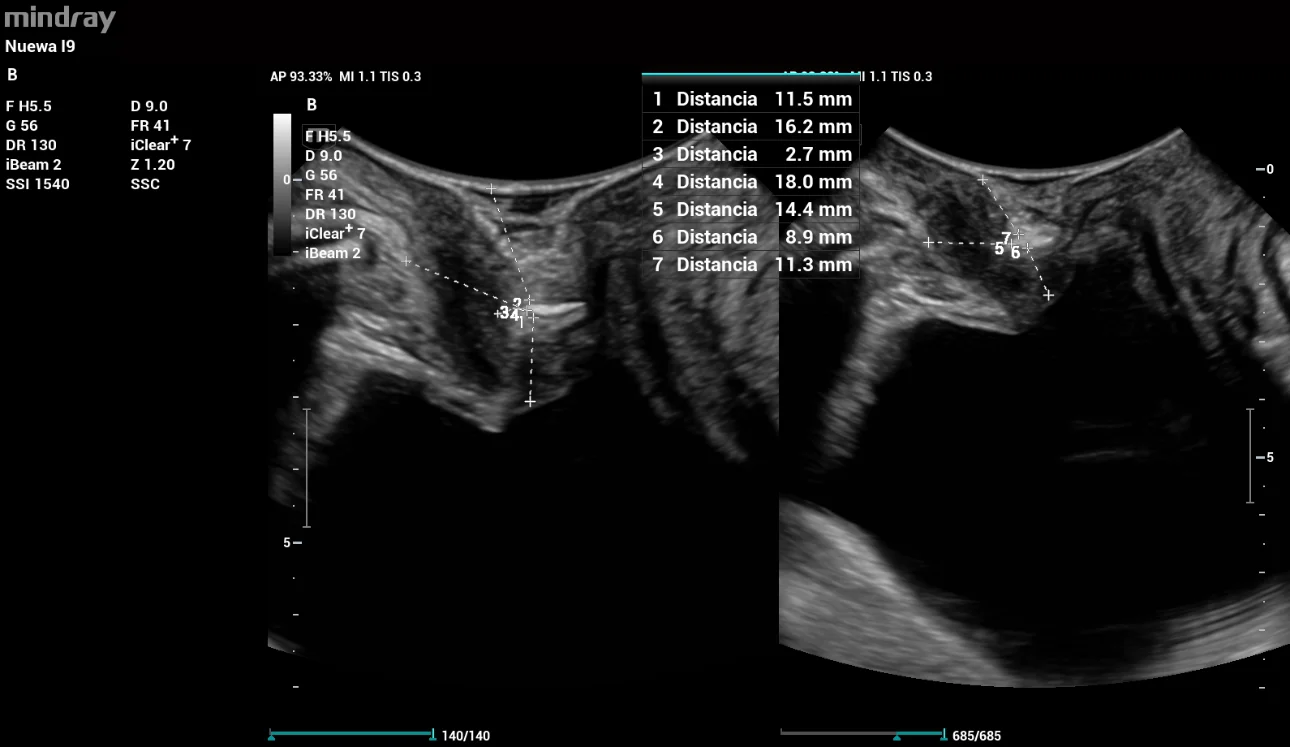

A periurethral evaluation was performed with an image suggestive of a MUS with a vertical vector (TVT), located at the junction of the middle and external urethral thirds (Figure 8).

The evaluation parameters of the MUS were: distance to the urethra 5mm (R); distance to the urethral meatus 4mm (R), 3mm (Val); distance to the bladder neck 16mm (R), 13mm (Val); pubic sling gap 17mm (R), 14mm (Val). No presence of prolapse mesh.

pelvic-floor-ultrasound-stress-incontinence-fig8

Figure 8: Presence of vertical vector sling (TVT) evaluated with HD Scope tool